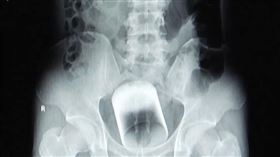

6公分瓷杯堵肛門求診 醫驚呆:怎麼塞的

一名中年男子因腹脹三天無法排便,肚子痛到無法忍受,趕...

2025/11/20 23:39

醉男「玻璃杯插肛門」拔不出 3天後求救

玩太嗨?一名47歲男子因為喝醉將玻璃杯插入肛門自娛,...

2023/03/27 12:24